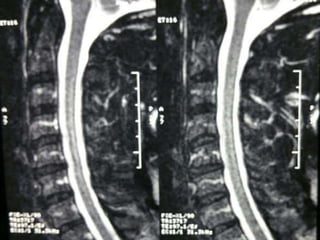

77 year old woman with h/o hand weakness/numbness/ataxia

Prior acdf 14 years ago

77 year oldwoman with h/o hand weakness/numbness/ataxia Prior acdf 14 years ago

Note:the black line directly posterior to the vertebral bodies and relative

Thinning of spinal cord, note normal disc height

Note:the black linedirectly posterior to the vertebral bodies and relative Thinning of spinal cord, note normal disc height